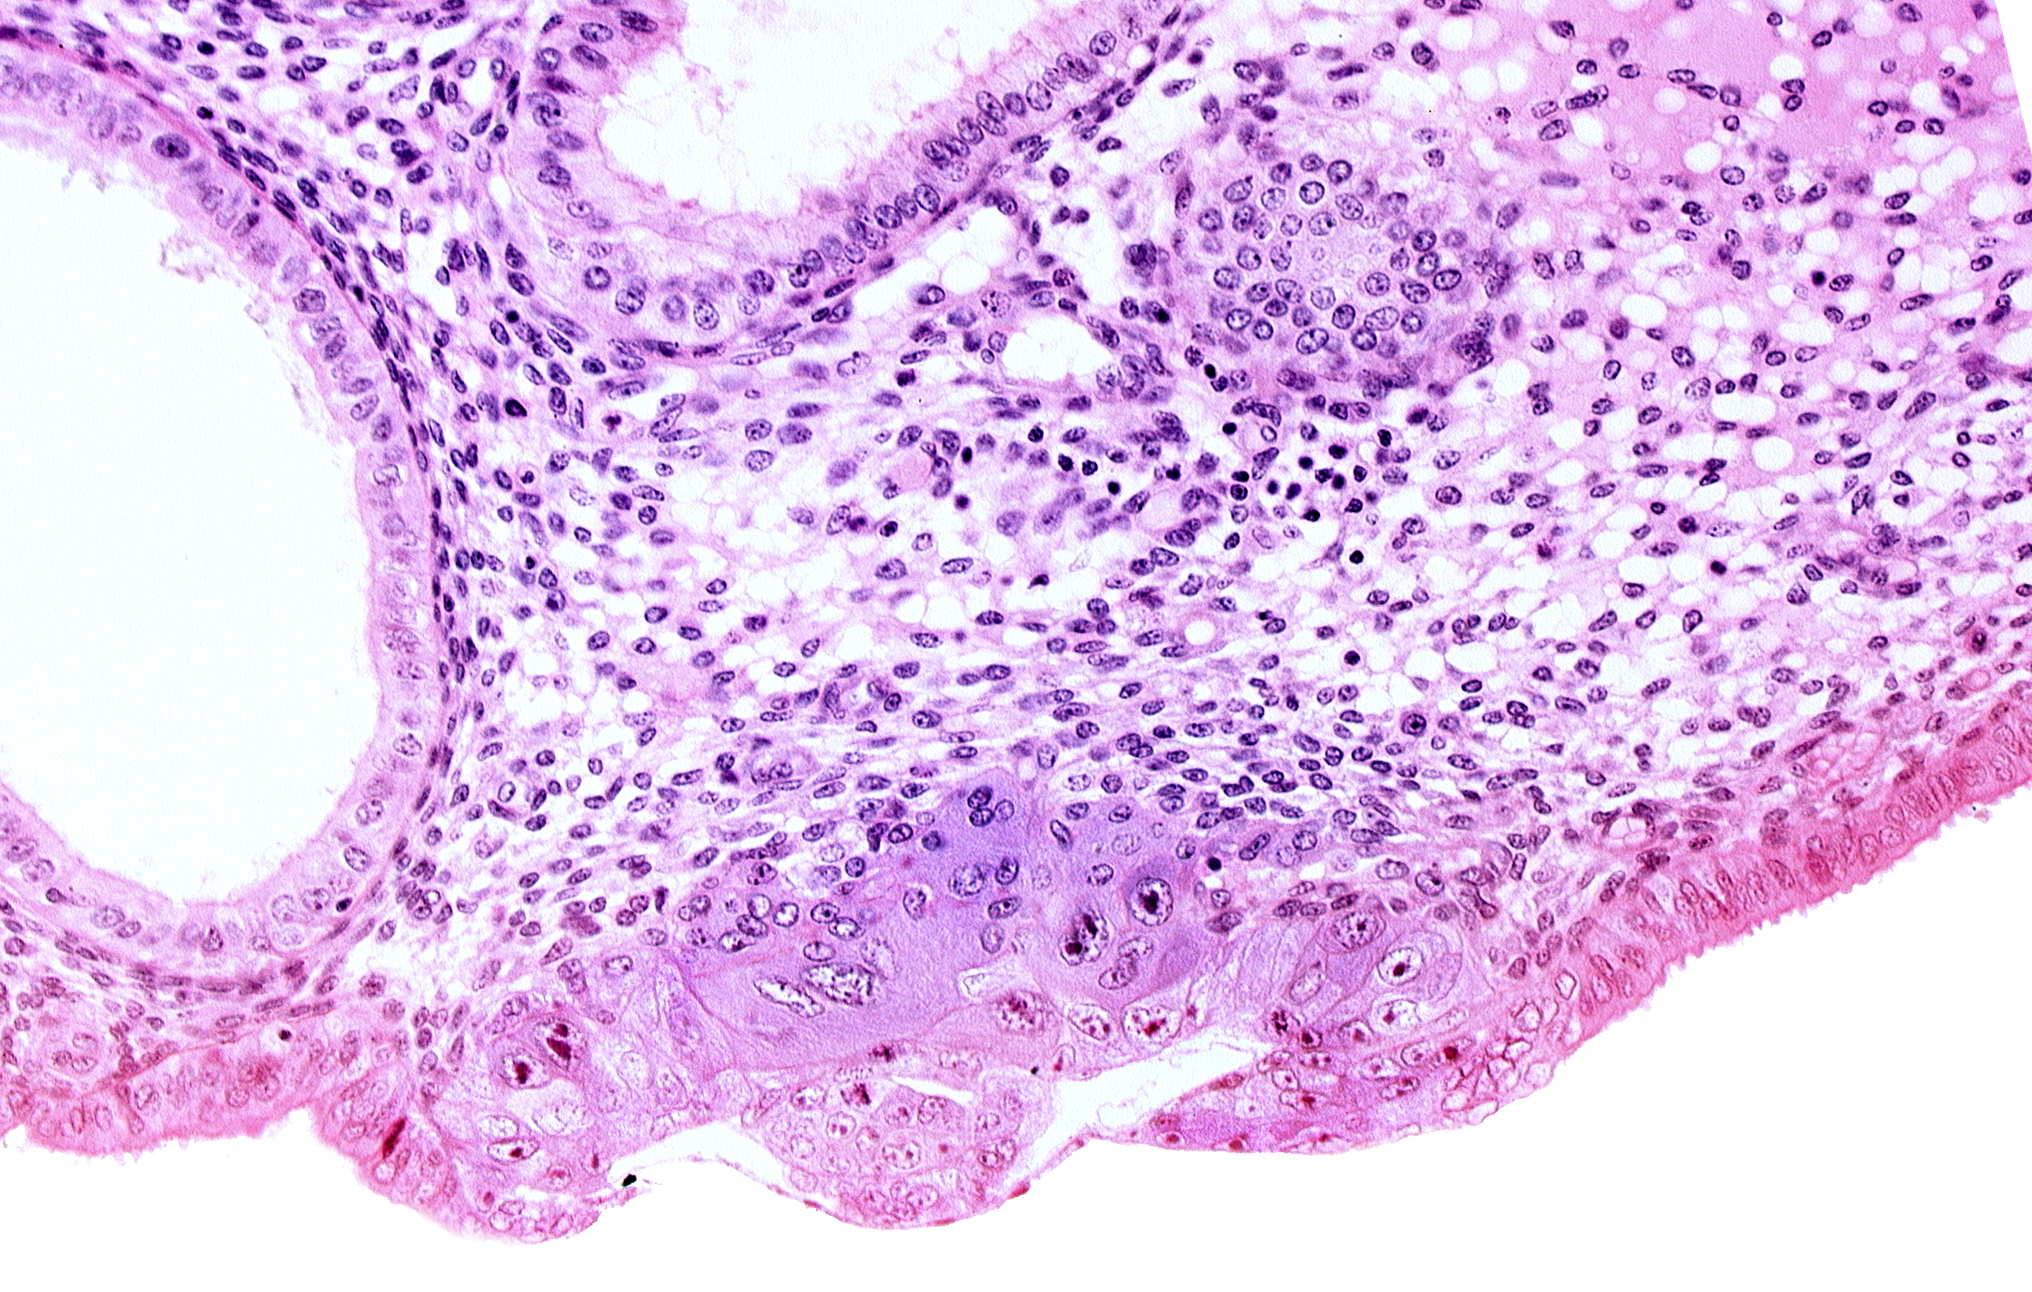

Carnegie Embryo #8020 | Location: 06-02-01

Keywords: amniotic cavity, blastocystic cavity (blastocoele), edematous endometrial stroma (decidua), endometrial epithelium, lumen of endometrial gland, membranous trophoblast at abembryonic pole

Source: The Virtual Human Embryo.